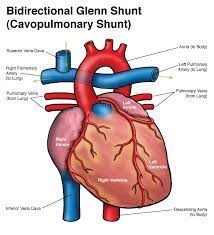

Overview

Package includes:

Days in hospital : 10 to 11 Days (For patient and one attendant)

Days in hotel : 14 Days (For patient and one attendant)

Room type in hospital : Shared

Room type in hotel : Private

Hotel category: Standard

Value added benefits of the BD Glenn:

Ø Doctor consultation charges

Ø Lab tests and diagnostic charges

Ø Room charges inside hospital during the procedure

Ø Surgeon Fee

Ø Nursing charges

Ø Hospital surgery suite charges

Ø Anesthesia charges

Ø Routine medicines and routine consumables (bandages, dressings etc.)

Ø Food and Beverages inside hospital stay for patient and one attendant.

Extra benefits:

ü Interpreter

ü Visa assistance

Ø Site tourism of the city

Ø Follow up with the doctor

Ø Airport pick up and drop

Ø Free online consultation with the doctor

Ø Priority appointments with the doctor

Ø Room upgrade from sharing to private